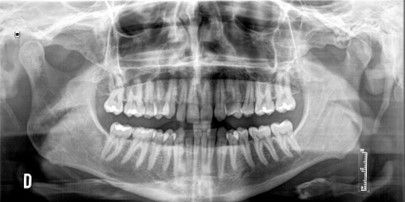

Se presenta un paciente varón de 34 años de edad, no fumador y sin antecedentes médico-quirúrgicos de interés (ASA I), que acudió a la consulta demandando una mejora en la estética de su sonrisa.

El paciente presentaba una agenesia congénita en el incisivo lateral superior izquierdo que había sido tratada previamente con ortodoncia para cerrar dicho espacio.

Tras el examen intraoral del paciente y el estudio radiográfico, se plantea la opción de tratamiento de abrir nuevamente el espacio mediante ortodoncia para rehabilitar la ausencia con un implante de circona, asegurando la estética que demandaba el paciente.

Case description: A clinical case of a 34-year-old man is presented, non-smoker and with no previous registered medical records (ASA I) who came to the dental clinic demanding an improvement in the aesthetics of his smile. The patient had a congenital agenesis of the right lateral incisor that had previously been treated with orthodontics to close the space. After the radiographic study and intraoral examination of the patient, the treatment option of reopening the space with a new phase of corrective orthodontics to rehabilitate the absence with a zirconia implant was proposed, ensuring the aesthetics demanded by the patient.